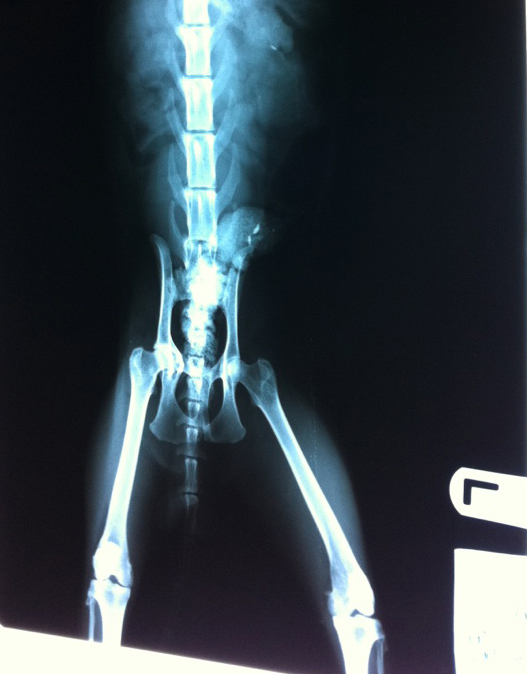

아래는 엑스레이사진과 검둥이 현재모습입니다

왼쪽 앞다리는 정상이고 오른쪽다리 특히 발부분 뼈가 많이 다쳤어요